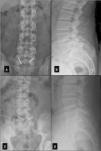

Since 1968, many surgical techniques used in repairing the pars defect of the vertebra have been reported. Technological advances are giving rise to new ways of obtaining the best outcome using less invasive methods, which are more accurate, simple and effective. To treat cases of spondylolysis such as pseudarthrosis, we used neuro-navigation and microscopy through a 2.5-cm skin incision to approach the pars defect, freshen the fracture and place a type of screw that, until now, has never been used for this purpose. This is a novel technique, which guarantees prolonged compression and sufficient stability to facilitate the prompt healing of the vertebra. We present 2 cases of L5 spondylolysis treated with our technique, a modification of Buck's technique. A detailed description of the screw selection, surgical technical details, follow-up and outcome are discussed.